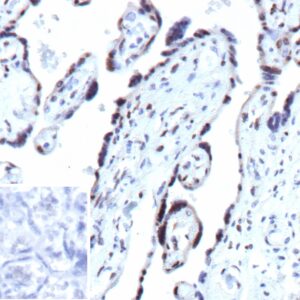

IHC analysis of formalin-fixed, paraffin-embedded human prostate. Strong nuclear staining using KIP1/1357 at 2ug/ml in PBS for 30min RT. HIER: Tris/EDTA, pH9.0, 45min. 2°C: HRP-polymer, 30min. DAB, 5min.